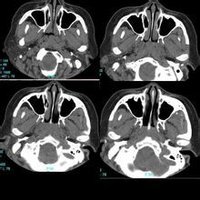

鼻咽部ct軸位平掃(層厚、層距均為5mm),圖像如下:

顳窩纖維血管瘤zjzjr發言:典型的血管纖維瘤,建議增強.

xulianj發言:建議增強。惡性腫瘤可能大。

腫塊引起翼齶窩擴大,壓迫上頜竇後壁,使其彎曲,變形,並向前移位是本病的特徵性表現。

增強呈均勻一致強化。